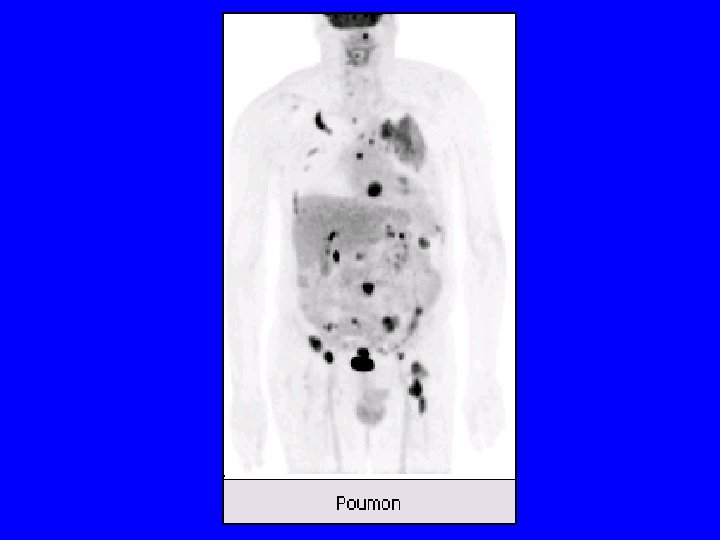

Indications • Diagnostic primaire – Dg différentiel masses pulmonaires – Bilan extension lymphomes H et NH, Kc pulm NPC, ORL et VADS , colo-rectaux, , mélanomes • Suivi thérapeutique précoce – lymphomes H et NH • Récidives et métastases – Kc pulmonaire NPC – Kc colo-rectaux – Kc ovaire…. .

Indications • AMM de 1998 • Cette AMM a été élargie, confirmant la TEP • bilan initial, le suivi thérapeutique et la recherche de récidive – tumeur broncho-pulmonaire, – des voies aéro-digestives supérieures, – colo-rectale, – d'un lymphome H et NH, – d'un mélanome